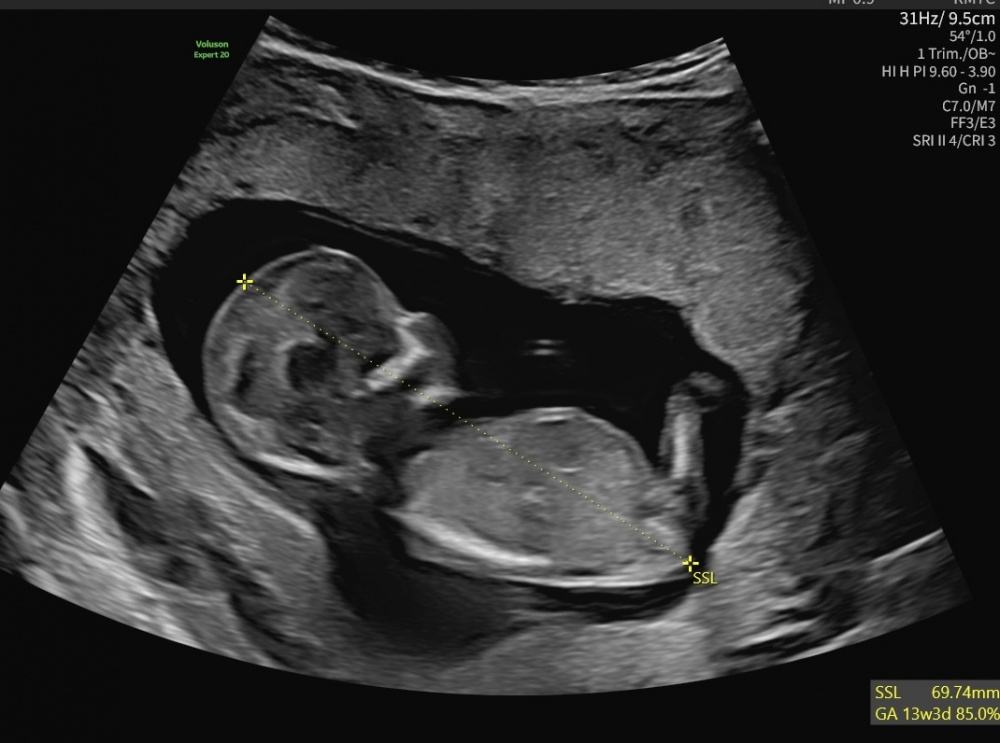

was würdet ihr hier laut dem NUB vermuten? Eher ein Mädchen oder einen Jungen? Danke LG Elli

ps.: Foto ist von 13+27qh5ewypzbxp.jpeg